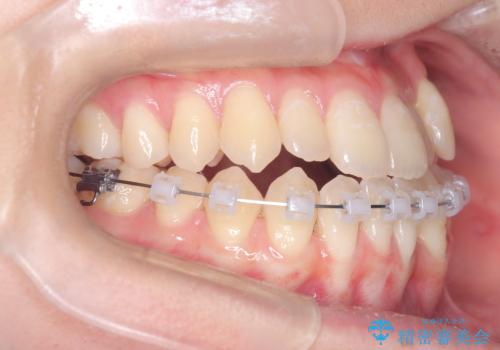

安全かつ確実に抜歯スペースを閉じ、咬み合わせを完成させるため、マウスピースから**ワイヤー矯正(マルチブラケット装置)**へ切り替えるリカバリープランを提案しました。

装置の変更と歯肉への配慮: ワイヤー矯正は歯の根(歯根)を平行に移動させる「歯体移動」を得意としています。本症例では、歯肉退縮を防ぐために、歯の傾きを精密にコントロールしながら抜歯スペースを閉じる必要がありました。ワイヤー装置を用いることで、インビザラインでは難しくなっていた三次元的な細かい調整を可能にしました。

リカバリーのプロセス: 適合が悪くなったインビザラインを一旦中止し、ブラケットを装着。停滞していた歯の移動を再開させ、上下の正中(中心)や奥歯の咬み合わせを一つひとつ整えていきました。